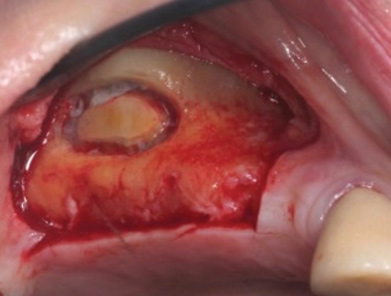

Dental implants are a predictable treatment option for the replacement of missing teeth. However, adjunctive surgical procedures may be required prior to implant placement. Sinus augmentation is indicated for cases in which deficient vertical bone height in the posterior region of the maxilla prevents dental implant placement. If inadequate residual bone height is present coronal to the maxillary sinus, the lateral sinus augmentation technique is recommended because it allows for the placement of larger volumes of graft material as well as greater access and visibility. In this technique, an osteotomy is made over the lateral sinus wall using rotary burs or a piezoelectric tip, taking care to keep the sinus mucosa intact (Figure 1). The sinus mucosa is then elevated (Figure 2), and a bone graft material is placed (Figure 3). Once healed, a significant increase in height and volume of bone can be seen radiographically (Figure 4 and Figure 5).

(2.) Elevation of Schneiderian membrane, demonstrating potential space prior to bone graft placement.

Figure 2